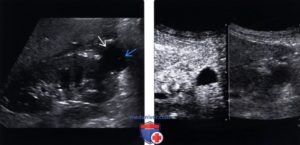

На первых порах наличие небольших кист в почках никак не дает о себе знать. Работа этого органа не нарушена, поэтому человек чувствует себя хорошо, и может выявить диагноз только на УЗИ.